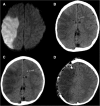

Malignant stroke occurs in a subgroup of patients suffering from ischemic cerebral infarction and is characterized by neurological deterioration due to progressive edema, raised intracranial pressure, and cerebral herniation. Decompressive craniectomy (DC) is a surgical technique aiming to open the "closed box" represented by the non-expandable skull in cases of refractory intracranial hypertension. It is a valuable modality in the armamentarium to treat patients with malignant stroke: the life-saving effect has been proven for both supratentorial and infratentorial DC in virtually all age groups. This leaves physicians with the difficult task to decide who will require early or preemptive surgery and who might benefit from postponing surgery until clear evidence of deterioration evolves. Together with the patient's relatives, physicians also have to ascertain whether the patient will have acceptable disability and quality of life in his or her presumed perception, based on preoperative predictions. This complex decision-making process can only be managed with interdisciplinary efforts and should be supported by continued research in the age of personalized medicine.